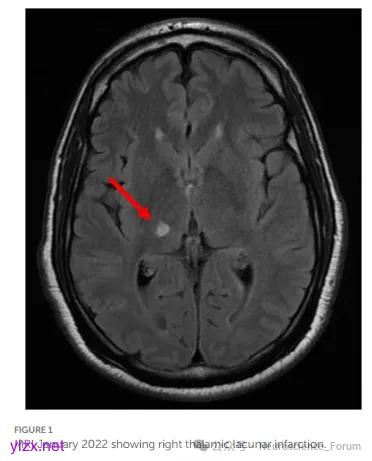

丘脑痛多继发于脑卒中,尤其是丘脑出血或梗死,典型症状包括:

目前诊断主要依赖病史与影像学检查,但缺乏特异性生物标志物,易误诊为周围神经病变。